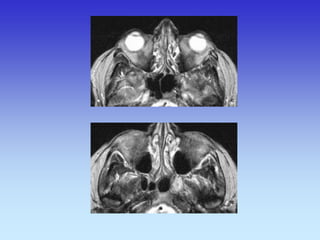

Lens

Cerebral aqueduct

Eye Ball

Optic Nerve

Optic Chiasm

Pons

Cerebellum

Temporal lobe

Lateral Rectus

muscle